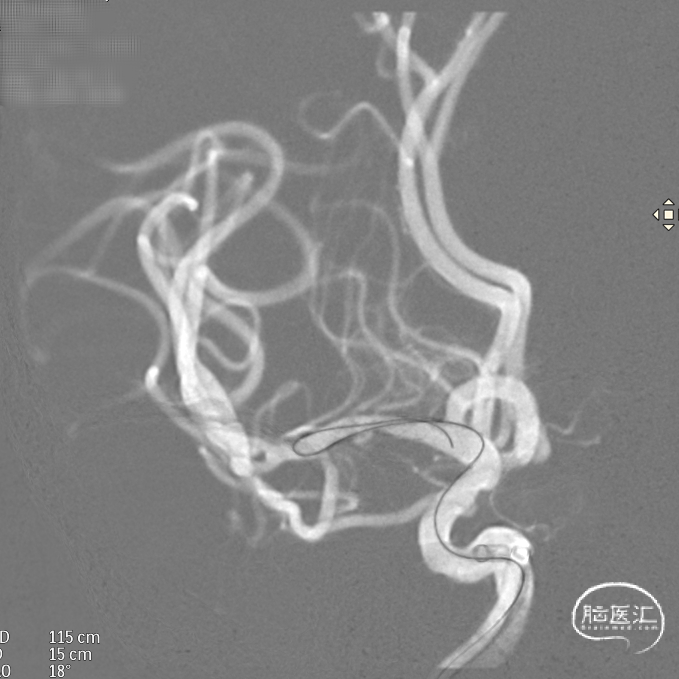

支架全部释放,调整张力,微导管通过支架,回收输送导丝。

支架内使用成襻微导丝进行按摩,使支架充分贴壁。

术后造影:支架充分覆盖动脉瘤瘤颈,贴壁良好,瘤体内可见造影剂滞留。

术后支架显影:定位精准,未覆盖颞前动脉及大脑前动脉。

强易达Choydar血流导向装置支架显影清晰,推送柔顺。

在弯道内支架轻松打开,不易扭结。

改良工艺提升镍钛支架的径向支撑力,贴壁良好。